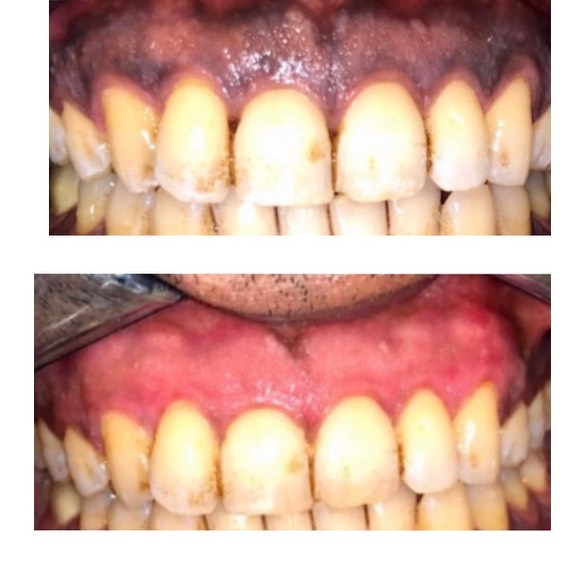

Siqaret və ya digər səbəblərdən yaranan rənglənmələrin götürülməsi

diş daşlarının təmizlənməsi

Zoom aparatı ilə 1 gündə dişlərin ağardılması

Air-flow